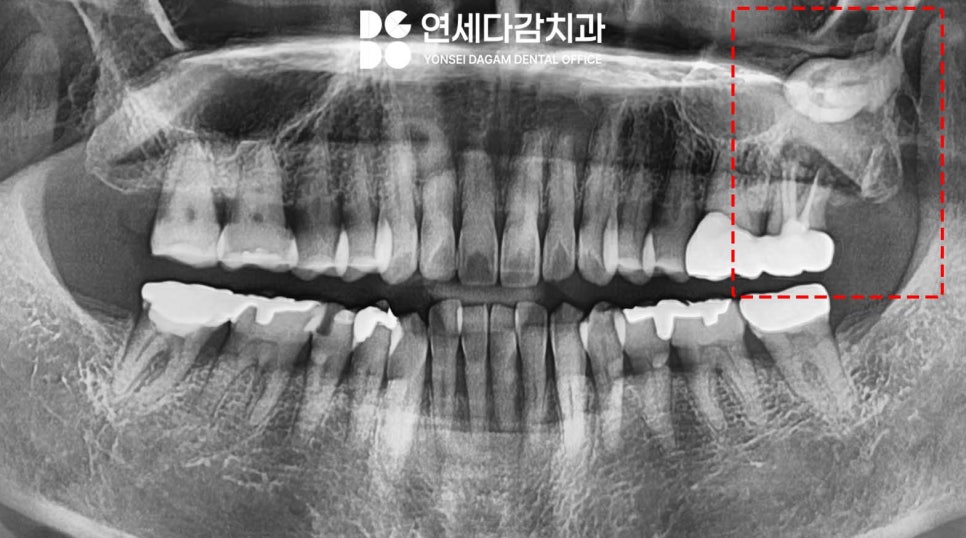

정밀 검사를 통해 환자 기준 왼쪽 위

어금니 주변을 살펴본 결과,

치아 뿌리 주변으로 심한 염증이

발생하여 치조골(치아를 지지하는 뼈)이

흡수된 상태였습니다.

이러한 상태는 이가 흔들리는

주된 원인이었습니다.

그뿐만 아니라

그 치아의 치근단(뿌리 끝) 부위 주변으로

비정상적으로 위치한

매복 사랑니가 있다는 것이었습니다.